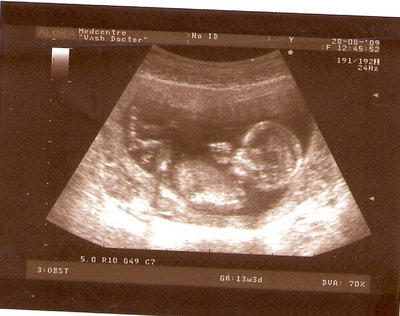

13 НЕД И 5 ДНЕЙ

| Вложения: |

3.jpg [ 96.81 КБ | Просмотров: 2441 ]

Nikisa писал(а): Foto prosto chudesnoe. A na kakom sroke uznali, chto sin.............. НА 13 НЕДЕЛЯХ.КАК РАЗ ВОТ В ЭТО узи, ОНО УМЕНЯ ВТОРОЕ БЫЛО. ЭТО КОНЕЧНО МАЛЕНЬКИЙ СРОК ДЛЯ ОПРЕДЕЛЕНИЯ ПОЛА. НО Я ПОПРОСИЛА ВРАЧА(ЭТО КТСТАТИВ РОССИИ БЫЛО) ХОТЯ БЫ ПРЕДПОЛОЖИТЬ. ЕЙ ВСЁ ТАКИ УДАЛОСЬ РАССМОТРЕТЬ.НУ ВООБЩЕМ ЧЕРЕЗ НЕСКОЛЬ ДНЕЙ ПОЙДУ К ВРАЧУ, УЖЕ АМЕРЕКАНСКОМУ И УЗНАЮ ТОЧНО. К ТОМУ ВРЕМЕНИ У МЕНЯ БУДЕТ СРОК 18 НЕДЕЛЬ. ХОТЕЛОСЬ БЫ ПОСМОТРЕТЬ НА ДРУГИЕ ФОТО НА ЭТОМ СРОКЕ ИЛИ БОЛЬШЕ. ТАК ЧТО ВЫКЛАДЫВАЙТЕ, ЕСЛИ НЕ ЖАЛКО!